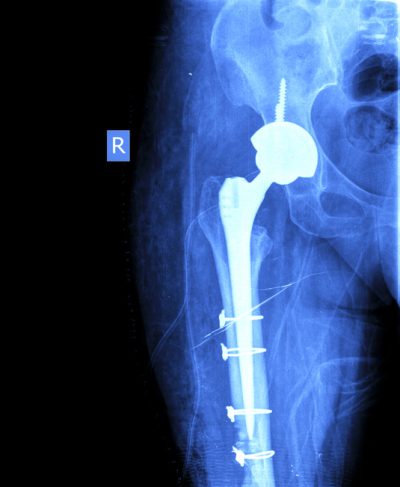

Certains gestes complémentaires sont parfois nécessaires pour enlever la prothèse et fixer correctement la suivante comme une ostéotomie fémorale d’exposition, l’apport de greffons osseux ou la pratique d’une ostéosynthèse par plaque, vis ou cerclage. ( voir radiographies ci-dessous).